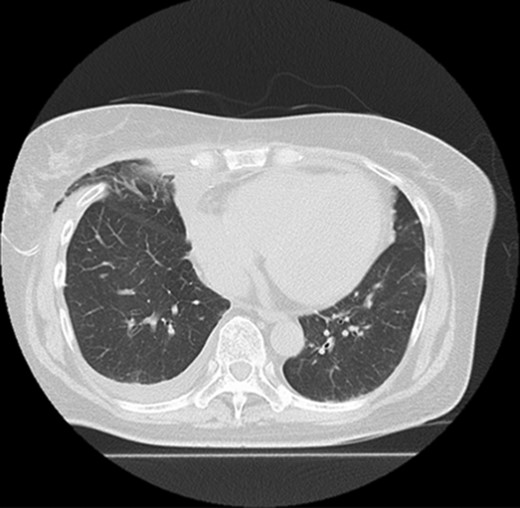

On follow-up CT at 1 month postoperatively, the upper lobe remained in the thoracic cavity and no sign of lung herniation was apparent (Fig. 3).

Follow-up CT shows that the lung hernia has returned to the thoracic cavity.